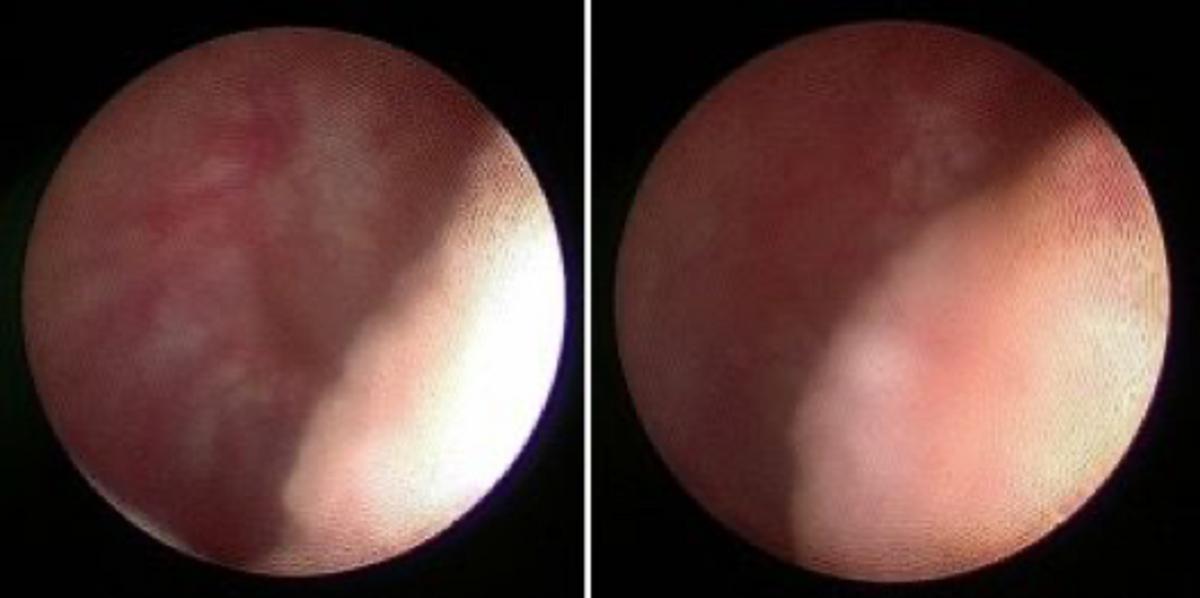

术中可见左侧射精管区域明显囊性扩张。

术中应用精囊镜+钬激光于薄膜处“开窗”(图A-C),可见多量淡黄色稠厚精液涌出(图D)。